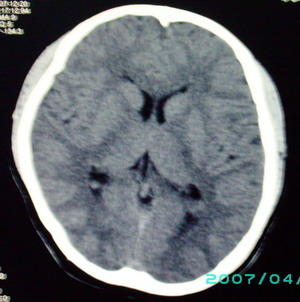

以下是引用九目段在2007-12-24 14:55:00的发言:[br]1,年轻女性[br]2,ct表现:左侧脑室三角区可见一不规则小明显强化的结节,中央见小低密度,侧脑室无扩张。[br]分析:[br]常见的有三种肿瘤好发三角区:[br]1,脉络丛乳头状瘤,好发于年轻者,明显强化,实性,分泌脑脊液,常伴有侧脑室扩大,肿瘤较小可以脑室扩大不明显,不能排除,但小结节尚不易形成坏死腔。[br]2,室管膜瘤,好发于儿童及青少年,明显强化,易坏死,大时伴脑室扩张。[br]3,脑膜瘤,明显强化,圆形,界请,无脑积水,一般不坏死。[br]诊断:[br]左侧脑室三角区结节,考虑室管膜瘤可能性大,不排除脉络丛乳头状瘤和脑膜瘤(因病史较长)。[br][br][本贴已被 九目段 于 2007-12-24 15:13:35 修改过]